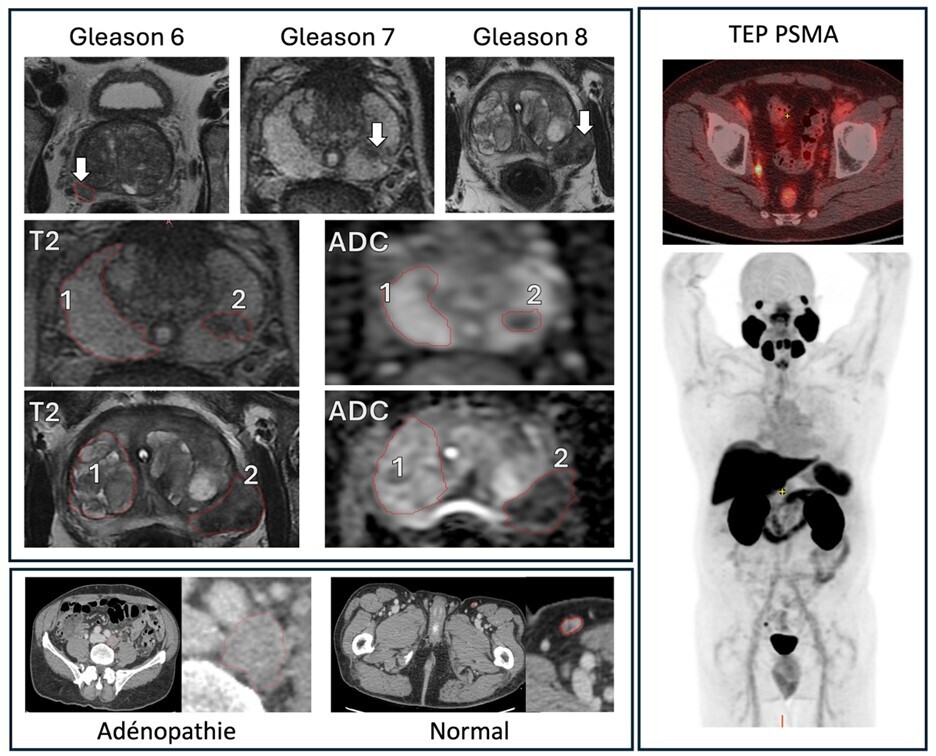

La sensibilité et la spécificité du taux de PSA ne sont pas absolues. Dans certains cas, l’IRM peut être utilisée pour évaluer la prostate et localiser les lésions suspectes. Elle est interprétée en utilisant les critères Prostate Imaging- Reporting and Data System (PI-RADS). PI-RADS est un ensemble de directives pour l’interprétation de l’IRM de la prostate améliorant la détection du cancer cliniquement significatif. La version 2 de PI-RADS met l’accent sur l’utilisation du coefficient d’atténuation de diffusion  (ADC) et de l’IRM pondérée en diffusion pour les anomalies de la zone périphérique, et sur l’IRM pondérée en T2 pour la zone de transition, simplifiant l’évaluation des images contrastées. En cas de forte suspicion de cancer de la prostate avec IRM et biopsies négatives, la TEP-TDM au PSMA (antigène membranaire spécifique de la prostate) permet la détection d’un cancer de la prostate cliniquement significatif chez environ la moitié des patients. Dans cette situation, la TEP-TDM au PSMA peut guider la biopsie de deuxième intention (fig. 1).

Lorsqu’un cancer de la prostate à haut risque (ou intermédiaire défavorable) selon la classification pronostique d’Amico est diagnostiqué, un bilan d’extension par examens d’imagerie complémentaires est réalisé. Ces examens visent à détecter les métastases lymphatiques et osseuses. Bien que l’imagerie conventionnelle (TDM thoraco-abdomino-pelvienne et tomo­scintigraphie osseuse) reste un standard, depuis 2021, la TEP-TDM au PSMA se généralise dans cette indication, avec une meilleure précision diagnostique sur l’atteinte ganglionnaire pelvienne et métastatique à distance et une accessibilité croissante sur le territoire français.5

Les performances de la TEP-TDM au PSMA sont ­supérieures à celles de l’imagerie conventionnelle (scanner et tomoscintigraphie osseuse) lors du bilan d’extension initial (lorsque celui-ci est indiqué) et dans le bilan d’extension des récidives biologiques (fig. 1).4 Elle peut également être utile, en deuxième intention, pour cibler les biopsies prostatiques.